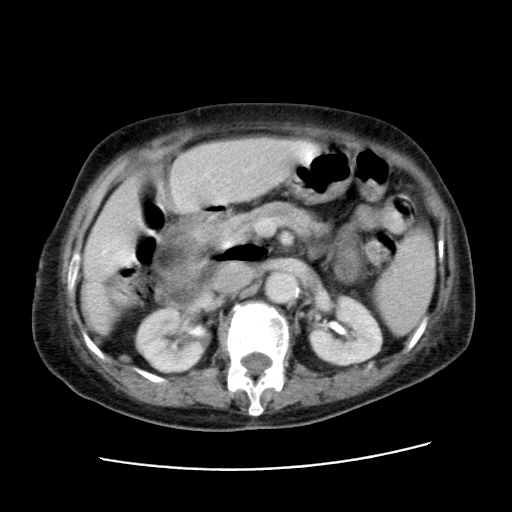

标题: CT25203:上腹部增强,看看

女,77.无不适

肝脏变异、异位胆囊,肝右叶肝内胆管结石并肝内胆管扩张。

肝右叶肝内胆管结石并肝内胆管扩张。

肝右叶肝内胆管结石并肝内胆管扩张。胆总管下段梗阻,考虑壶腹部占位。

右侧肝内胆管局限性扩张,其内密度不均匀,扩张的胆管壁增厚,考虑肝内胆管炎合并结石可能性大

肝右叶肝内胆管结石并肝内胆管扩张。胆总管下段梗阻,考虑壶腹部占位。支持